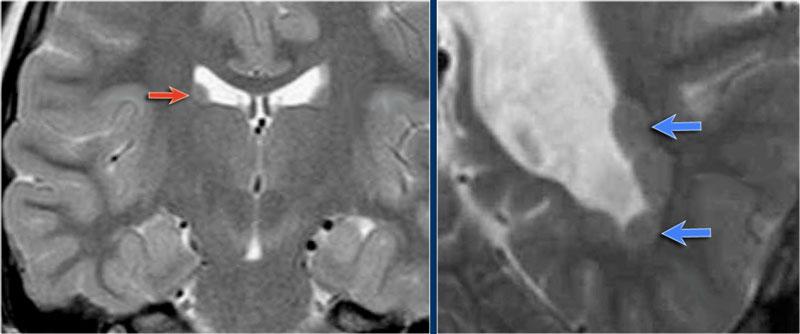

Hình ảnh T2W và FLAIR mặt phẳng coronal cho thấy xơ cứng thùy thái dương trong bên phải.

Lưu ý tình trạng mất thể tích, biểu hiện của teo não, gây giãn thứ phát sừng thái dương của não thất bên.

Tín hiệu cao trong hải mã phản ánh tình trạng gliosis.

Hình ảnh cho thấy xơ cứng thùy thái dương trong với hải mã tăng tín hiệu và teo nhỏ (mũi tên đỏ), kèm theo giãn thứ phát sừng thái dương trái của não thất bên trái.

Cũng cần lưu ý tình trạng tăng tín hiệu dưới vỏ não kết hợp ở thùy thái dương trái, gợi ý loạn sản vỏ não khu trú.

Xơ cứng thùy thái dương trong bên trái. Gliosis kín đáo của hải mã trái (mũi tên xanh dương) và teo não (mũi tên vàng).

Bệnh nhân 35 tuổi với động kinh thùy thái dương kháng trị.

MRI cho thấy tăng tín hiệu kín đáo của hải mã trái trên chuỗi xung FLAIR axial (mũi tên xanh dương) và teo hải mã trái trên hình ảnh coronal (mũi tên vàng).

Bệnh nhân được điều trị thành công bằng phẫu thuật cắt hạnh nhân – hải mã bên trái.